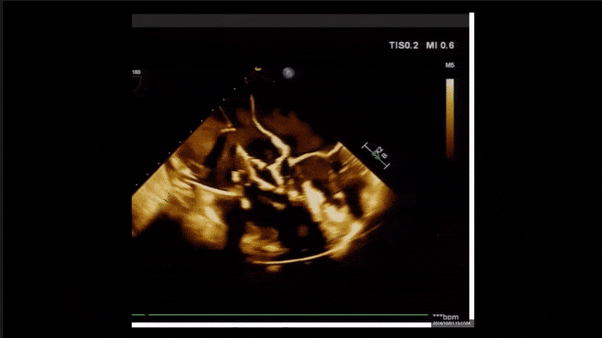

術后即刻返流

術后即刻返流三維

術后三維超聲

術后即刻經食道超聲可見,三尖瓣假體瓣膜位置合適,牛心包瓣葉運動狀態良好,開閉正常,瓣周及瓣葉對合緣處未見明顯返流,心電圖及心包狀態較術前無明顯變化。